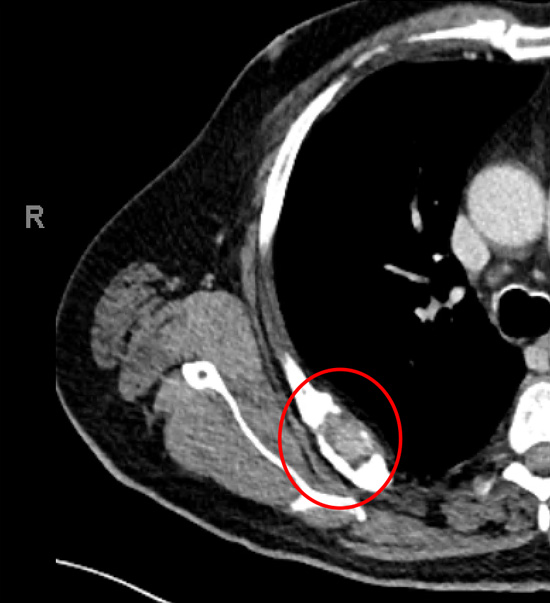

Secondary (metastasis) cancer to the 7th right rib causing pain on moving the shoulder (red rings) on chest CT (left) and PET (right). The original cancer was from the thyroid. The rib and cancer were surgically removed